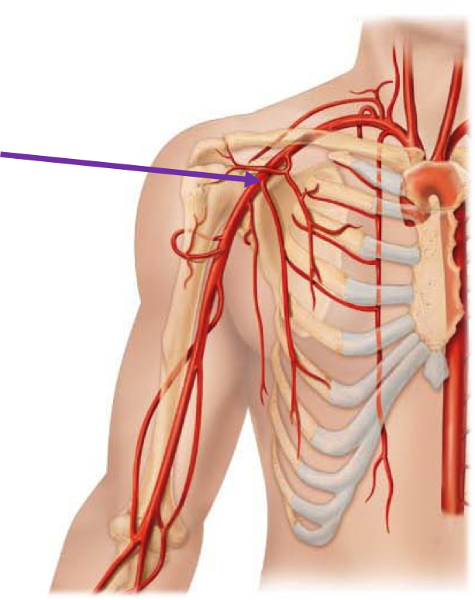

Axillary artery/vein

Brachial artery

Subclavian artery/vein